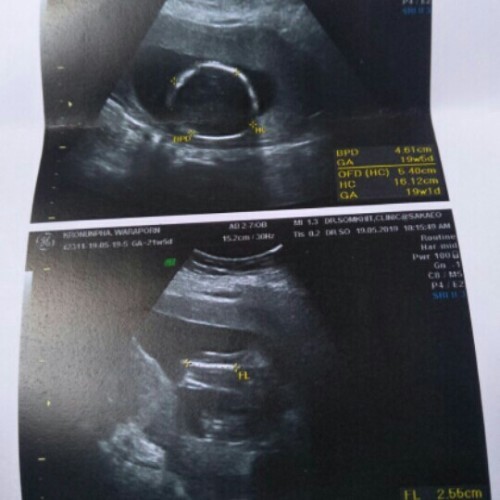

หมอบอกชาย18w

18 week จ้า

18 weeks 🥰